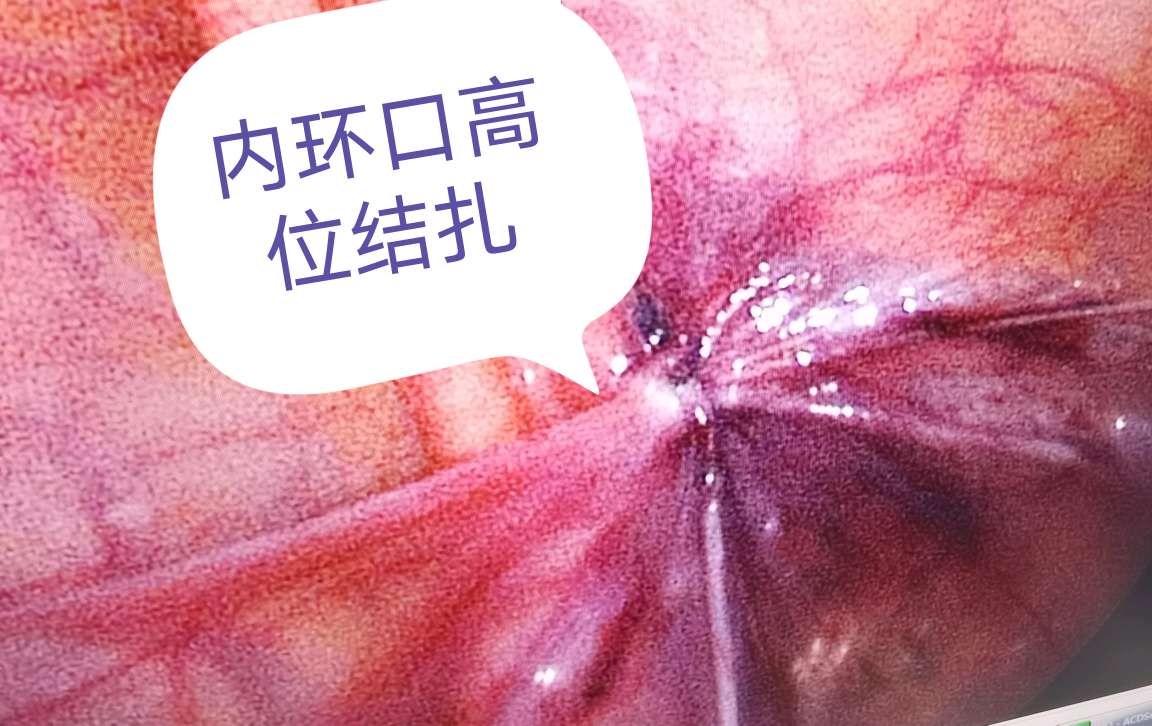

教科书上明确指出:因腹股沟斜疝容易嵌顿,腹股沟疝一经诊断后,应尽早进行手术治疗,以免发生嵌顿疝导致严重后果。手术治疗腹股沟疝已相当安全,可不受年龄限制。我科曾成功对出生7天宝宝的腹股沟斜疝进行腹腔镜手术(因腹股沟斜疝嵌顿)。腹腔镜下疝囊高位结扎术在我国技术成熟,其优点为术中精索损伤小、术后切口小,另外腹腔镜可以探查到对侧内环口未闭合时同时给予预防性结扎,传统开刀手术存在对侧再发需再次手术可能。

腹腔镜下内环口高位结扎